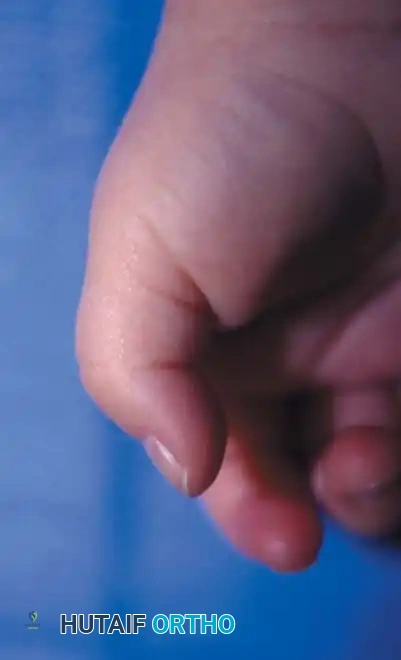

Clinical presentation of a congenital trigger thumb in a 2-year-old child, demonstrating the characteristic fixed flexion posture of the interphalangeal (IP) joint.

Prospective studies of over 5,765 newborns have failed to reveal a single case of congenital trigger thumb at birth, supporting the consensus that the condition is more accurately described as acquired in infancy. It is frequently unnoticed until the child reaches 1 to 2 years of age, presenting as a relatively fixed flexion posture of the interphalangeal (IP) joint.

Even with passive force, full extension of the IP joint may be impossible. The abnormal clicking or snapping that is the hallmark of adult trigger digits is rarely the presenting complaint in children.